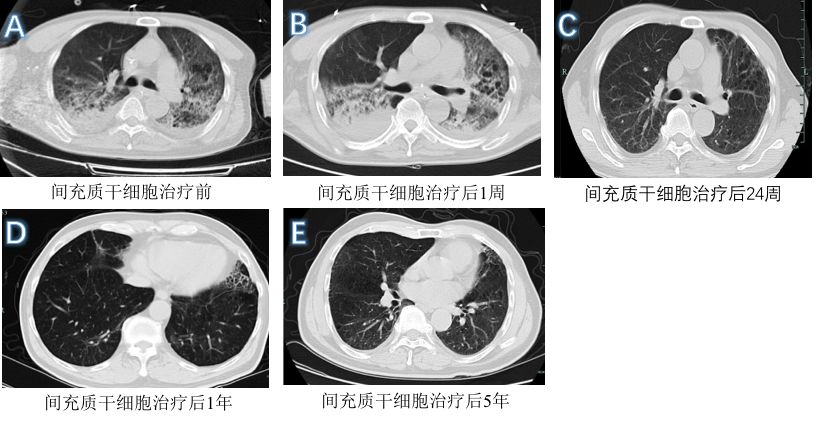

治疗结果显示:接受宫血MSC治疗组ARDS患者的死亡率显著低于对照组,两者分别为17.6%和54.5%。在接受宫血MSC治疗期间,未发现MSC输注相关急性毒性反应或其他严重不良反应。在为期5年的随访内,未观察到宫血MSC对患者的身体产生不良影响,且胸部CT显示患者肺部功能恢复良好(图1)。对比没有接受宫血MSC治疗的患者,接受MSC治疗的患者的肝功能、肾功能及肌酸激酶等指标都有显著改善。该研究表明,宫血MSC治疗是救治H7N9诱导的严重肺损伤的安全有效的疗法。

图1.MSC治疗后一位患者的胸部CT图像。(A)在MSC移植之前, 肺部CT表现为磨玻璃样改变、渗出实变病灶、纤维条索。随访(B)1周,(C)24周,(D)1年和(E)5年期间肺部CT表现:空气支气管征,磨玻璃样改变,支气管扩张,纤维条索,局部胸膜增厚和胸水。随着随访时间的延长,肺部CT表现均有较好改善。